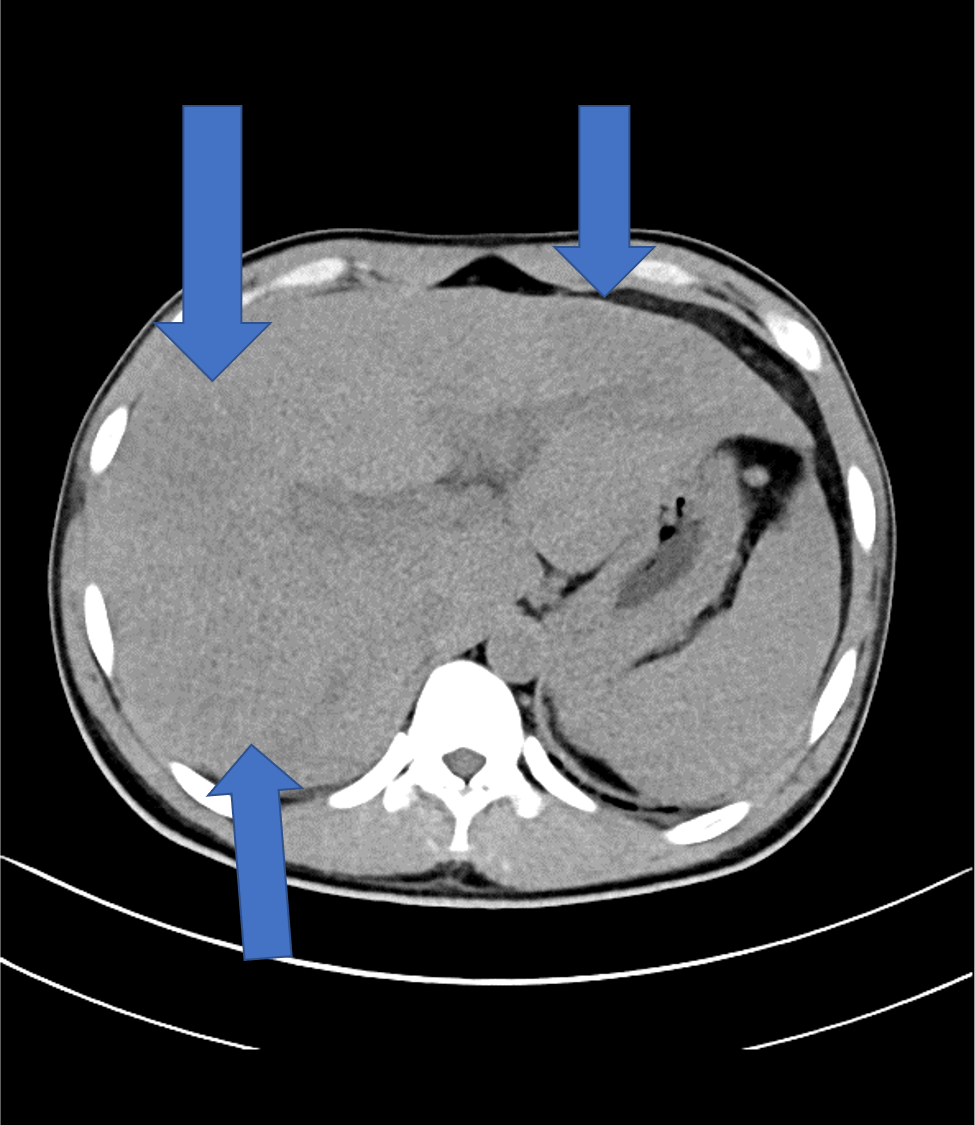

肝内に地図状の乏血性の領域や、病変内に門脈枝の貫通像がみられ、これらは好酸球増多症における肝病変として矛盾しない所見であった。

病変は結節状~地図状などとさまざまな形態で、腫瘤を形成することもあればしないこともある。本症例は腫瘤形成はしていない。

動脈相では乏血性の領域が見られ、門脈相では最もコントラストが強まる。平衡相では遅延性濃染がみられる。本症例はこれらの所見に合致した。

そして本症例でも見られているが、病変内に門脈が貫通する所見が好酸球増多症における肝病変として特徴的であり、これを門脈相で捉えられることもダイナミックCTを撮像する利点である。